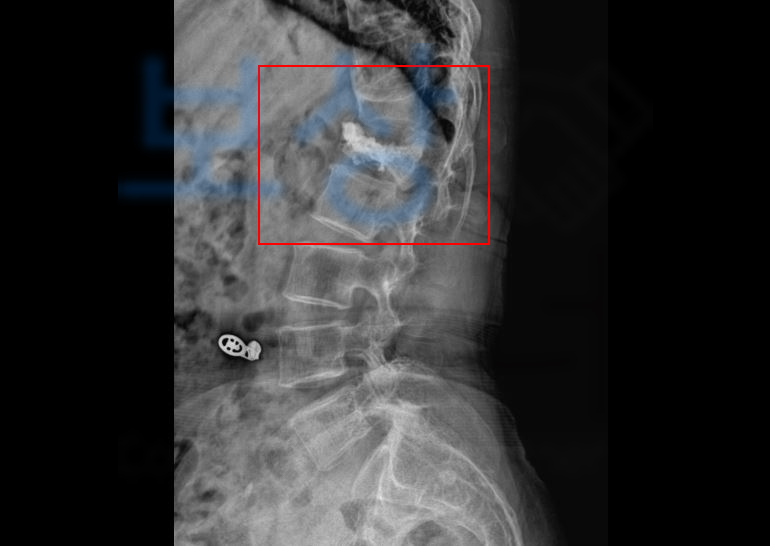

이 사고로 인해 정@@님은 요추 1번 골절 진단을 받으셨고 허리 보조기를 착용하시며 보존적 치료를 시행하게 되었습니다. 먼저 버스 회사 측으로부터 보상 받을 수 있습니다. 하지만 많은 분들이 버스회사에서** 나몰라라** 식이다, 혹은 버스회사에서 **경찰에 먼저 ** 신고부터 하라고 했다 등등 여러 이유들로 보험 접수부터

정@@님 또한 여유를 가지며 치료를 받으신 뒤 진단에 대한 장해 진단을 위해 전문의로부터 손해배상에 사용되는 장해진단서 발급을 하게 되었고

위와 같이 발급된 장해진단서를 기초로 합의금을 산정하여 청구를 하게 되었습니다. 물론 사고 당시 과실이나 정@@님의 기왕증으로 인해 보험금을 대폭 삭감하려는 시도가 있었지만

마찬가지로 보험금 청구용(AMA)의 후유장해 진단서 발급을 진행하게되었고 그 결과 척추에 심한 기형 50% 해당되었습니다.